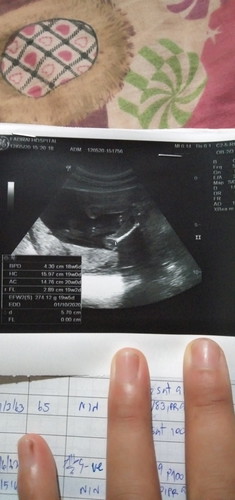

หมอบอกเหมือนเห็นจู๋แต่ยังไม่100%เพราะน้องยังเล็ก อยากถามแม่ๆว่าเห็นผู้หญิงหรือผู้ชายอยากให้แม่ๆดูช่วยให้หน่อยค่ะ

ของเราไปซาวด์มา เมื่อวันที่20/5/63 หมอบอกว่ายังม่คอนเฟิร์ม แต่เหมือนจะเป็นจู๋แต่ไม่100%เหมือนกันคะ ตอนนี้ 25w4bแล้วคะ

ของเรารุ้เพศตอน16wเลยจ้าเห็นจู๋ชัดมากเด็กผุ้ชายจะเห็นใวกว่าผุ้หญิงค่ะ ของแม่18wแล้วน่าจะชัดและชัวแล้วนะค่ะ

ของเราตอนแรก13wหมอบอกจู๋เริ่มออกมาละ ตอนนั้นหมอยังไม่คอนเฟิร์ม พอมา17+5 หมอว่าคอนเฟิร์มค่ะ ผู้ชาย

เหมือนจะเปนชายนะแม่

สงสัยจะชายค่ะแม่

เท่าที่ดู ชายจ้าแม่